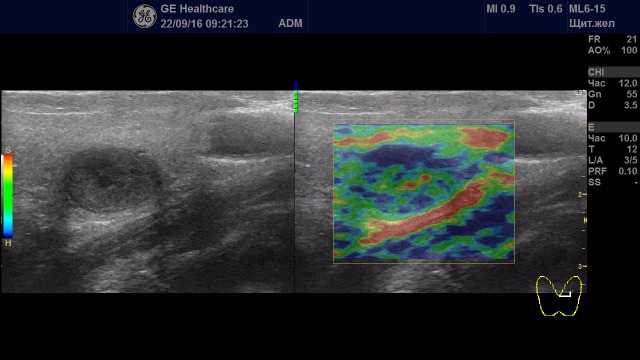

Образования с удовлетворительной эластичностью (тип I-III)